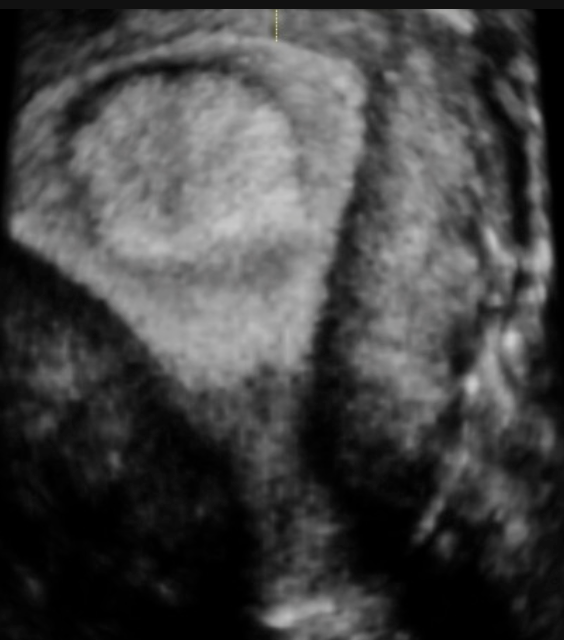

O diagnóstico inicial geralmente é suspeitado por exames de imagem, sendo os mais utilizados:

Fonte: IPGO Medicina da Reprodução (https://ipgo.com.br/as-causas-de-infertilidade-na-mulher-e-os-exames-para-o-diagnostico/)